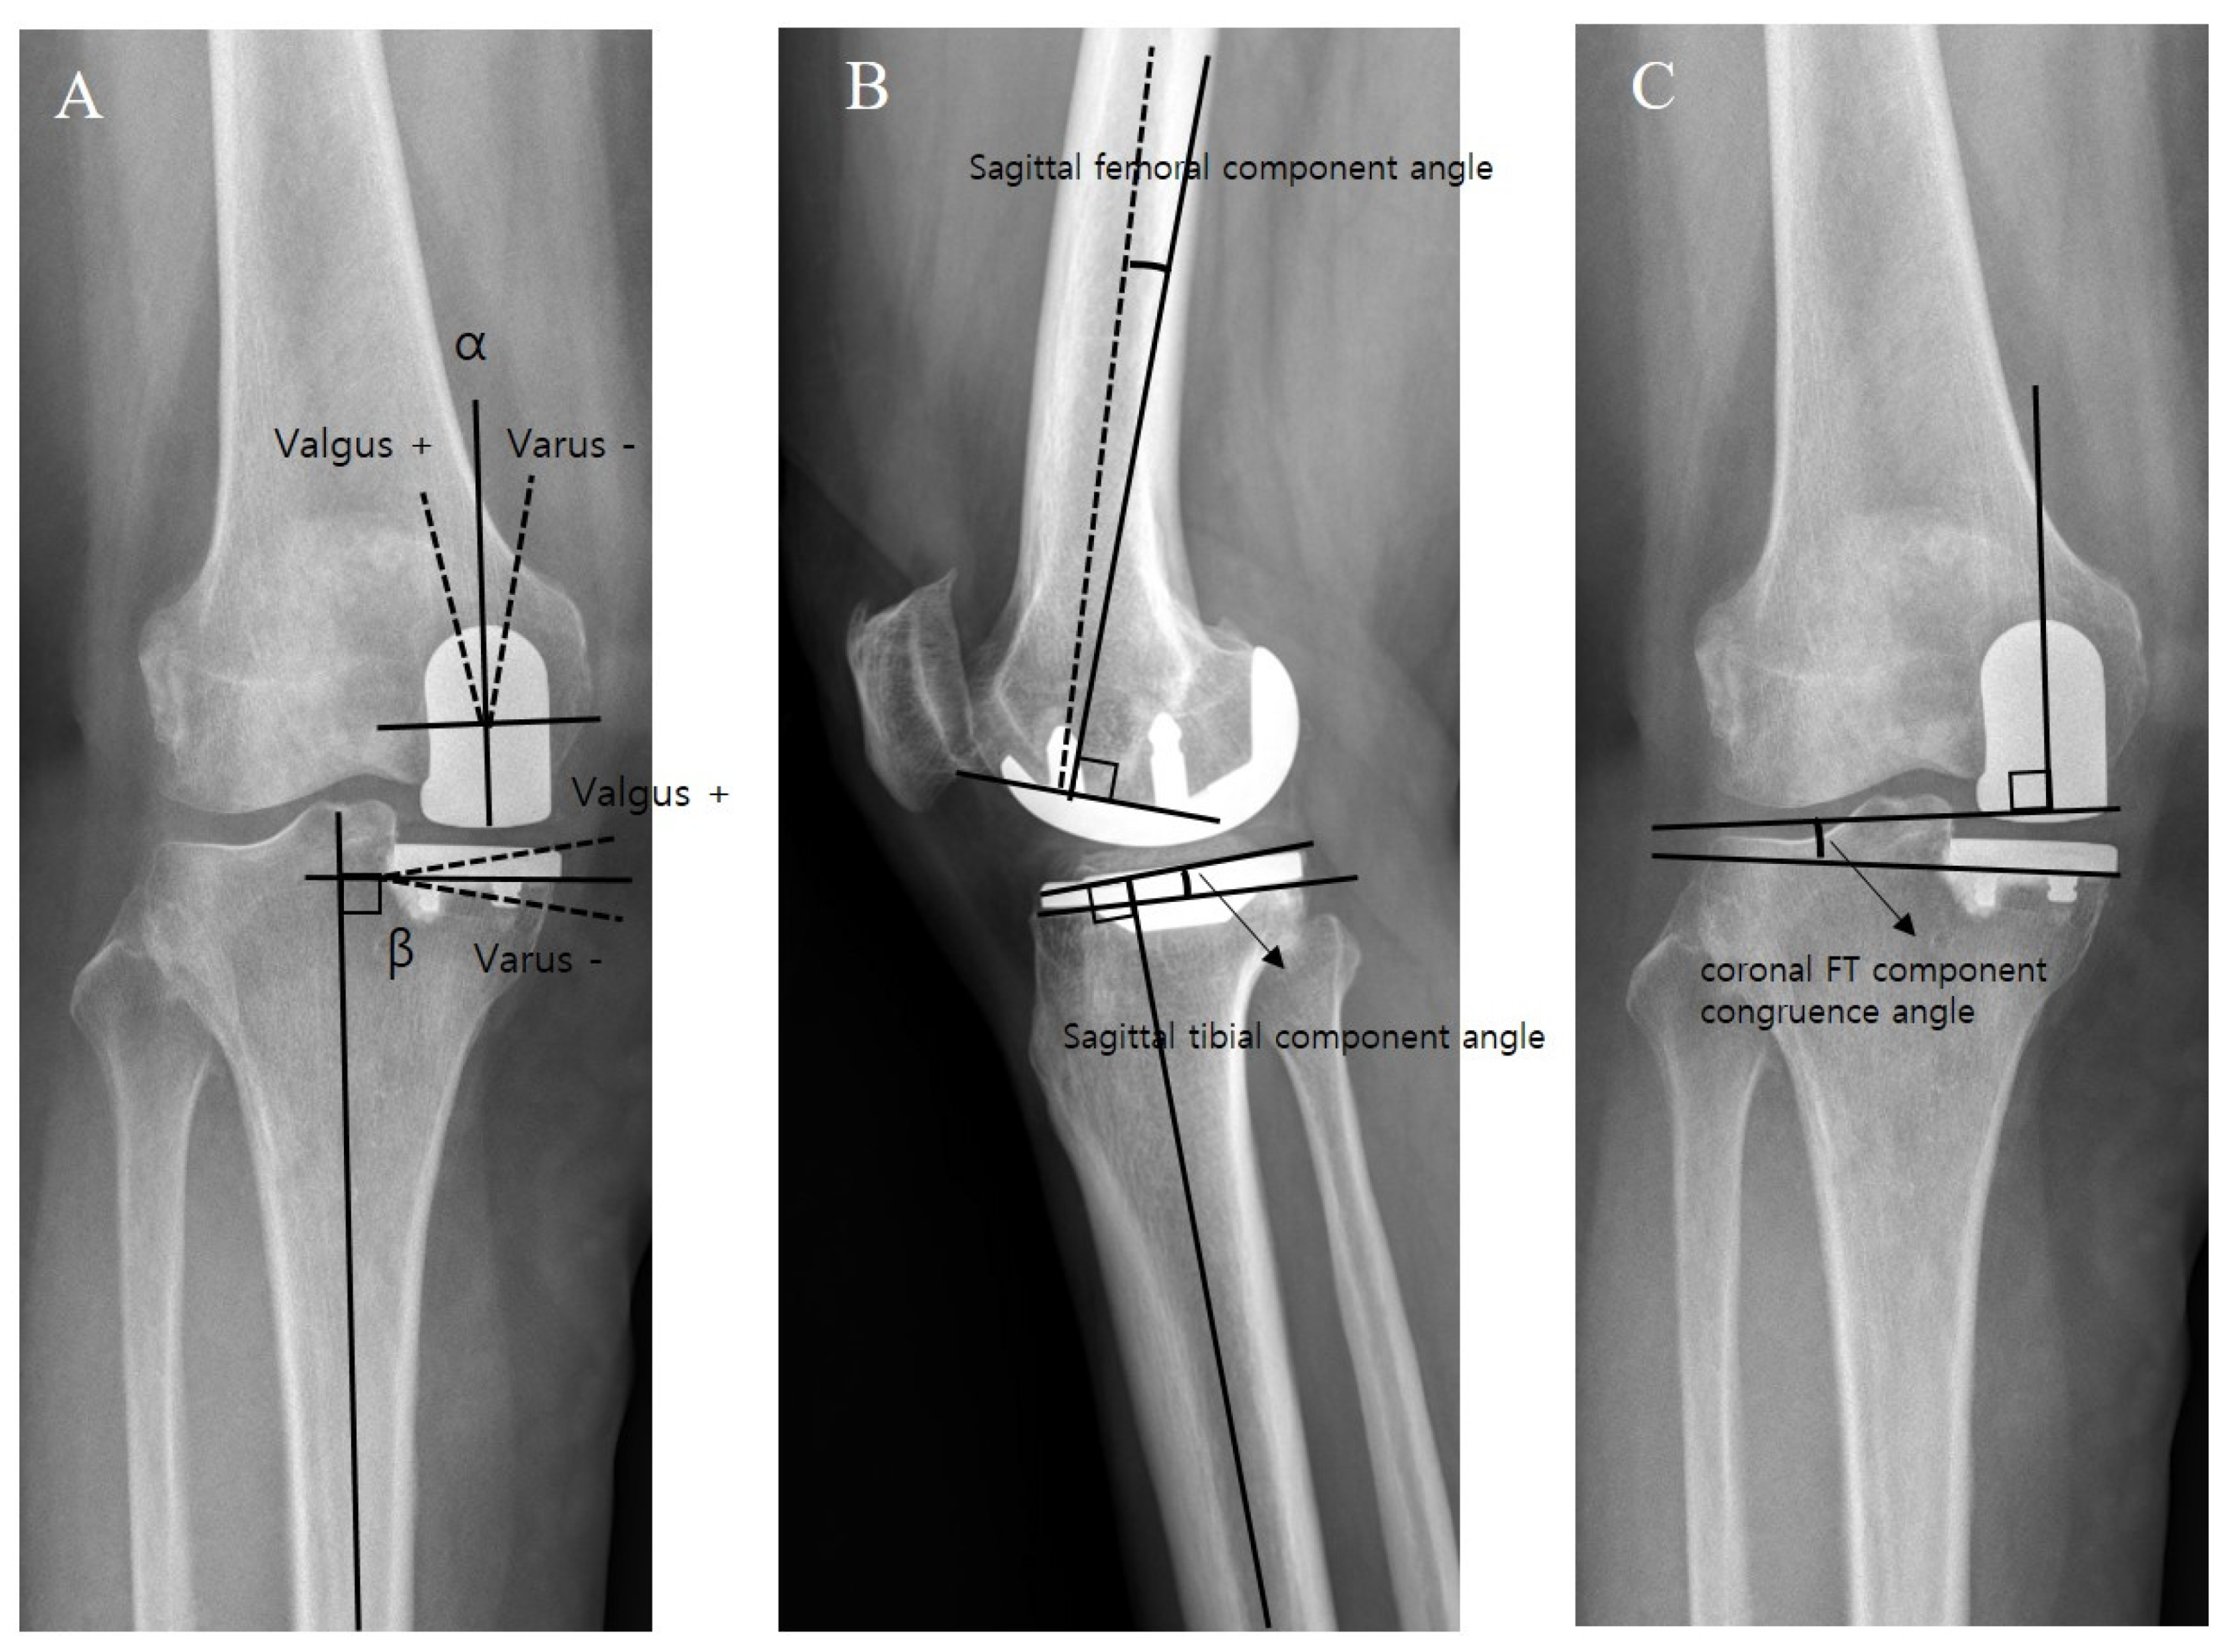

4. Clinical and Radiological Assessment

| Coronal femoral component angle (α) (°) | 2.4 ± 4.9 | −1.1 ± 3.2 | <0.001 |

| Coronal tibial component angle (β) (°) | −1.0 ± 4.3 | −3.0 ± 2.4 | 0.001 |

| Coronal FT component congruence angle (°) | 3.4 ± 4.5 | 1.9 ± 2.6 | 0.028 |